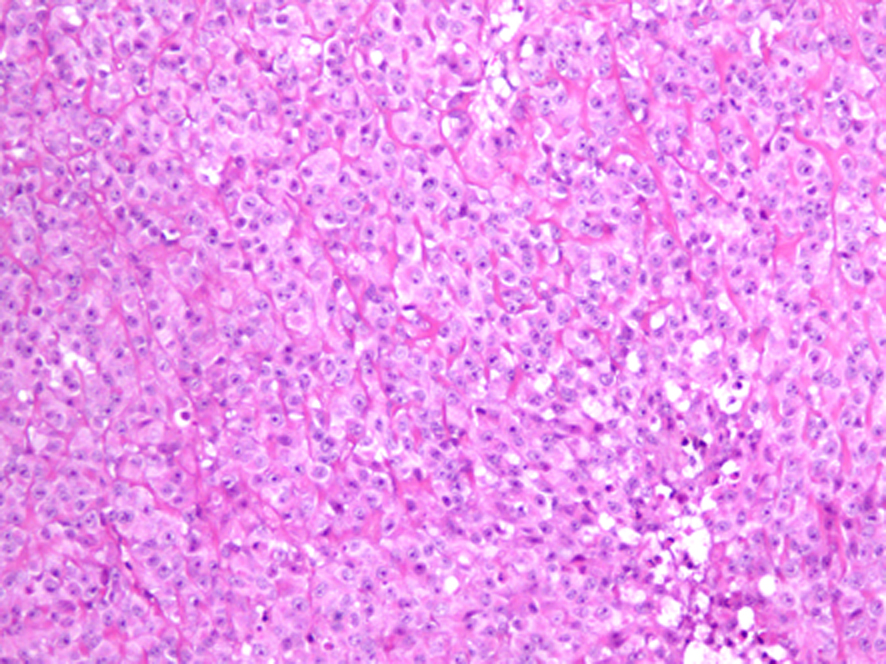

Follow-up CT scan and MRI done after 6 months were negative for tumor recurrence. Ten months after the initial presentation, patient presented with an enlarging lump over the surgical site with headache, vomiting and 12 pounds weight loss. MRI of the brain revealed three new enhancing soft tissue lesions at the original tumor site and one at the deep posterior margin of the previous surgical cavity. Positron emission tomography (PET) scan did not show any evidence of distant metastasis. Patient underwent gross total resection of the tumor. Pathology confirmed the diagnosis of grade 3 SEF, more aggressive than the initial presentation (Fig. 2). Post-operative course was uneventful and MRI of the brain demonstrated no residual lesion. Patient was started on chemotherapy with Doxorubicin and Ifosfamide with Mesna. He also underwent external beam cranial irradiation and completed 6 cycles of chemotherapy. At the end of his last cycle of chemotherapy and 19 months after the initial diagnosis, he presented with headache, vomiting, back pain and weight loss. MRI showed cranial and spinal metastasis. There were new enhancing lesions in the right frontal lobe and tumor infiltration of the epidural and subarachnoid spaces from thoracic to sacral areas. Patient's clinical status deteriorated with obstructive hydrocephalus and paraplegia and he died within a month.

![]() Click for large image | Figure 2. Light microscopic picture of SEF showing tumor cells arranged in hyalinized stroma (hematoxylin and eosin х 10). |

Imaging and histopathology are the primary modes of diagnosis. Bone involvement presents as lytic lesions in X-ray. CT scan or MRI results depend on the site of the tumor. Typical histology of SEF consists of epithelioid cells arranged in strands, nests, and/or sheets, in a fibrotic and hyalinized stroma [5]. Mitotic figures are either scant or absent, and necrosis is uncommon. Although histomorphology of SEF suggests the tumor to be low grade, it could manifest signs of high-grade tumor clinically. SEF belongs to the family of fibrosing fibrosarcomas and appears to be the most malignant variant of this family of low-grade fibrosarcomas [6, 7]. The only immunostaining marker consistently reported positive, as in our patient, is Vimentin which is a general marker for soft tissue sarcomas and therefore not specific for SEF [3].